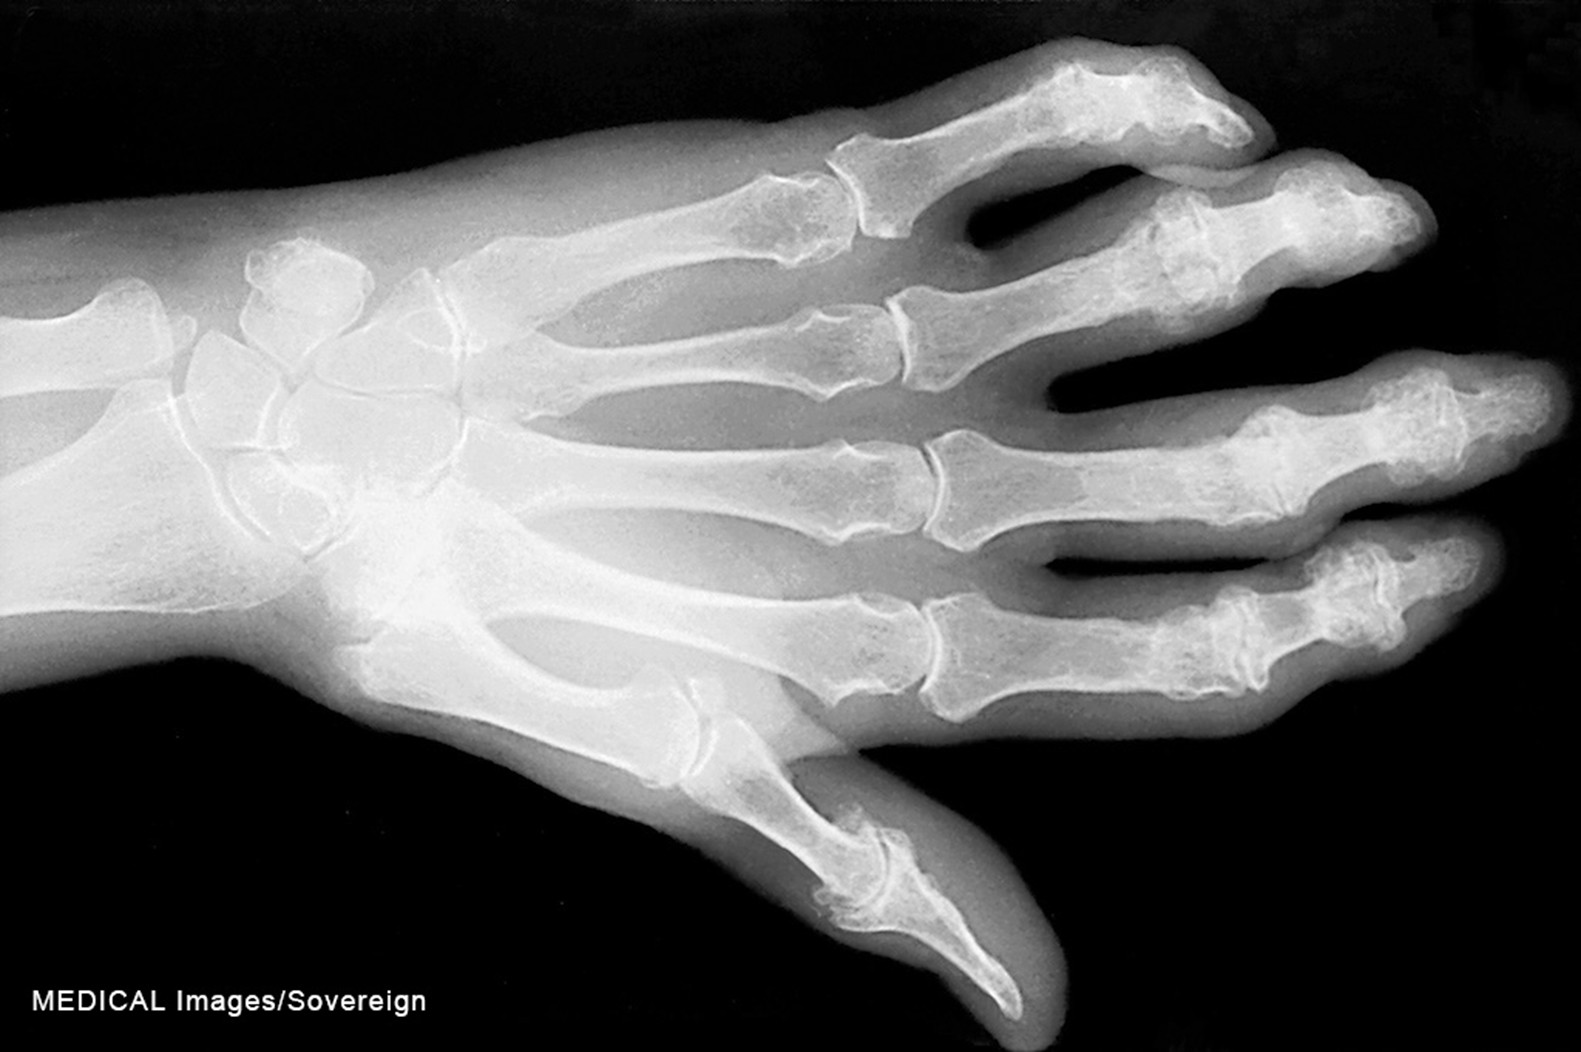

While OA may have unilateral joint involvement, individuals with RA characteristically have bilateral joint involvement and disability. Most causes have an insidious onset, while a smaller percentage, around 15%, may present with an acute onset (Rogers, 2023). Systemic signs and symptoms such as fever, weakness, fatigue, weight loss, and generalized aches and stiffness are typically the first presentation, followed by more local signs and symptoms such as joint tenderness, pain, and stiffness (CDC, 2024b; Rogers, 2023). Joint stiffness in the morning, commonly caused by synovitis, may last 30 minutes to several hours. The most common sites of RA include the wrists, metacarpophalangeal joints, and proximal interphalangeal joints. RA affects these smaller joints initially, followed by larger joints as the condition progresses (Rogers, 2023). The hands may become deformed, and patients may exhibit swan-neck deformities and ulnar deviation due to edema, joint destruction, or subluxation (refer to Figure 4; England, 2025; Rogers, 2023). In addition, patients may experience Boutonniere deformities, which present with hyperextension of the distal interphalangeal joints and flexion of the proximal interphalangeal joints. Over time, with long-standing RA, the cervical spine may become impacted, causing neck discomfort, occipital headaches, and muscle weakness in the upper arms (England, 2025).

Figure 4

Swan-neck deformity

Diagnosis

A diagnosis of RA is confirmed using a physical assessment, serum laboratory tests, and imaging (CDC, 2024b). A history and physical evaluation should be performed to assess for pain, disability, joint tenderness, edema, and temperature changes. The joint may have a spongy-like feel due to inflammation and synovial thickening (Rogers, 2023). The serum laboratory tests will include the erythrocyte sedimentation rate (ESR), C-reactive protein (CRP), rheumatoid factor (RF), and anticitrullinated peptide antibodies (ACPA; Baker, 2024; Rogers, 2023). However, RF is not diagnostic, as only 45% to 75% of individuals with the condition may have a positive RF (Rogers, 2023). An elevated ESR and CRP indicate the presence of inflammation. If the laboratory findings demonstrate a high RF, the patient is likely experiencing systemic effects of RA (Baker, 2024).

Radiographs are recommended for all patients with suspected RA. Radiographs may be normal in the early stages of RA, and changes on radiographs are not required for diagnosis. Other imaging tests include ultrasound and magnetic resonance imaging (MRI), which may be more sensitive at detecting bony erosion, a later manifestation of RA. Imaging tests are utilized to assess progression and the effectiveness of RA treatment. Synovial fluid may be examined for markers of inflammation (Baker, 2024).